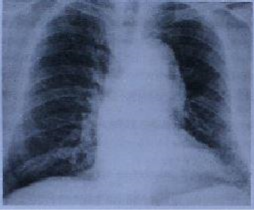

Um senhor hipertenso de 71 anos apresenta dor torácica súbita e intensa na ausência de alterações eletrocardiográficas, com a imagem radiográfica de tórax apresentada abaixo. Um ecocardiograma transtorácico realizado à beira do leito não identificou alteração contrátil segmentar do ventrículo esquerdo ou derrame pericárdico; a pressão sistólica arterial pulmonar foi normal. Qual exame mais indicado para esclarecimento do quadro?